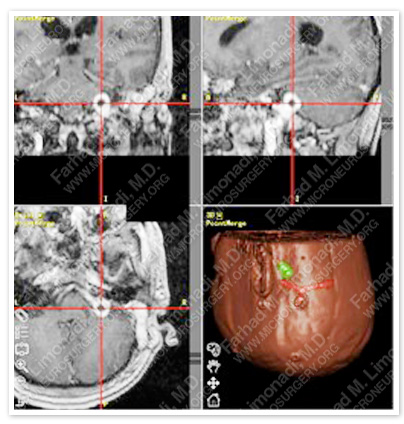

Imaging

Computer navigation is used to pin point the location of tumor. Tumor is shown in green in the right lower picture and is under the hairpin on MRIs.